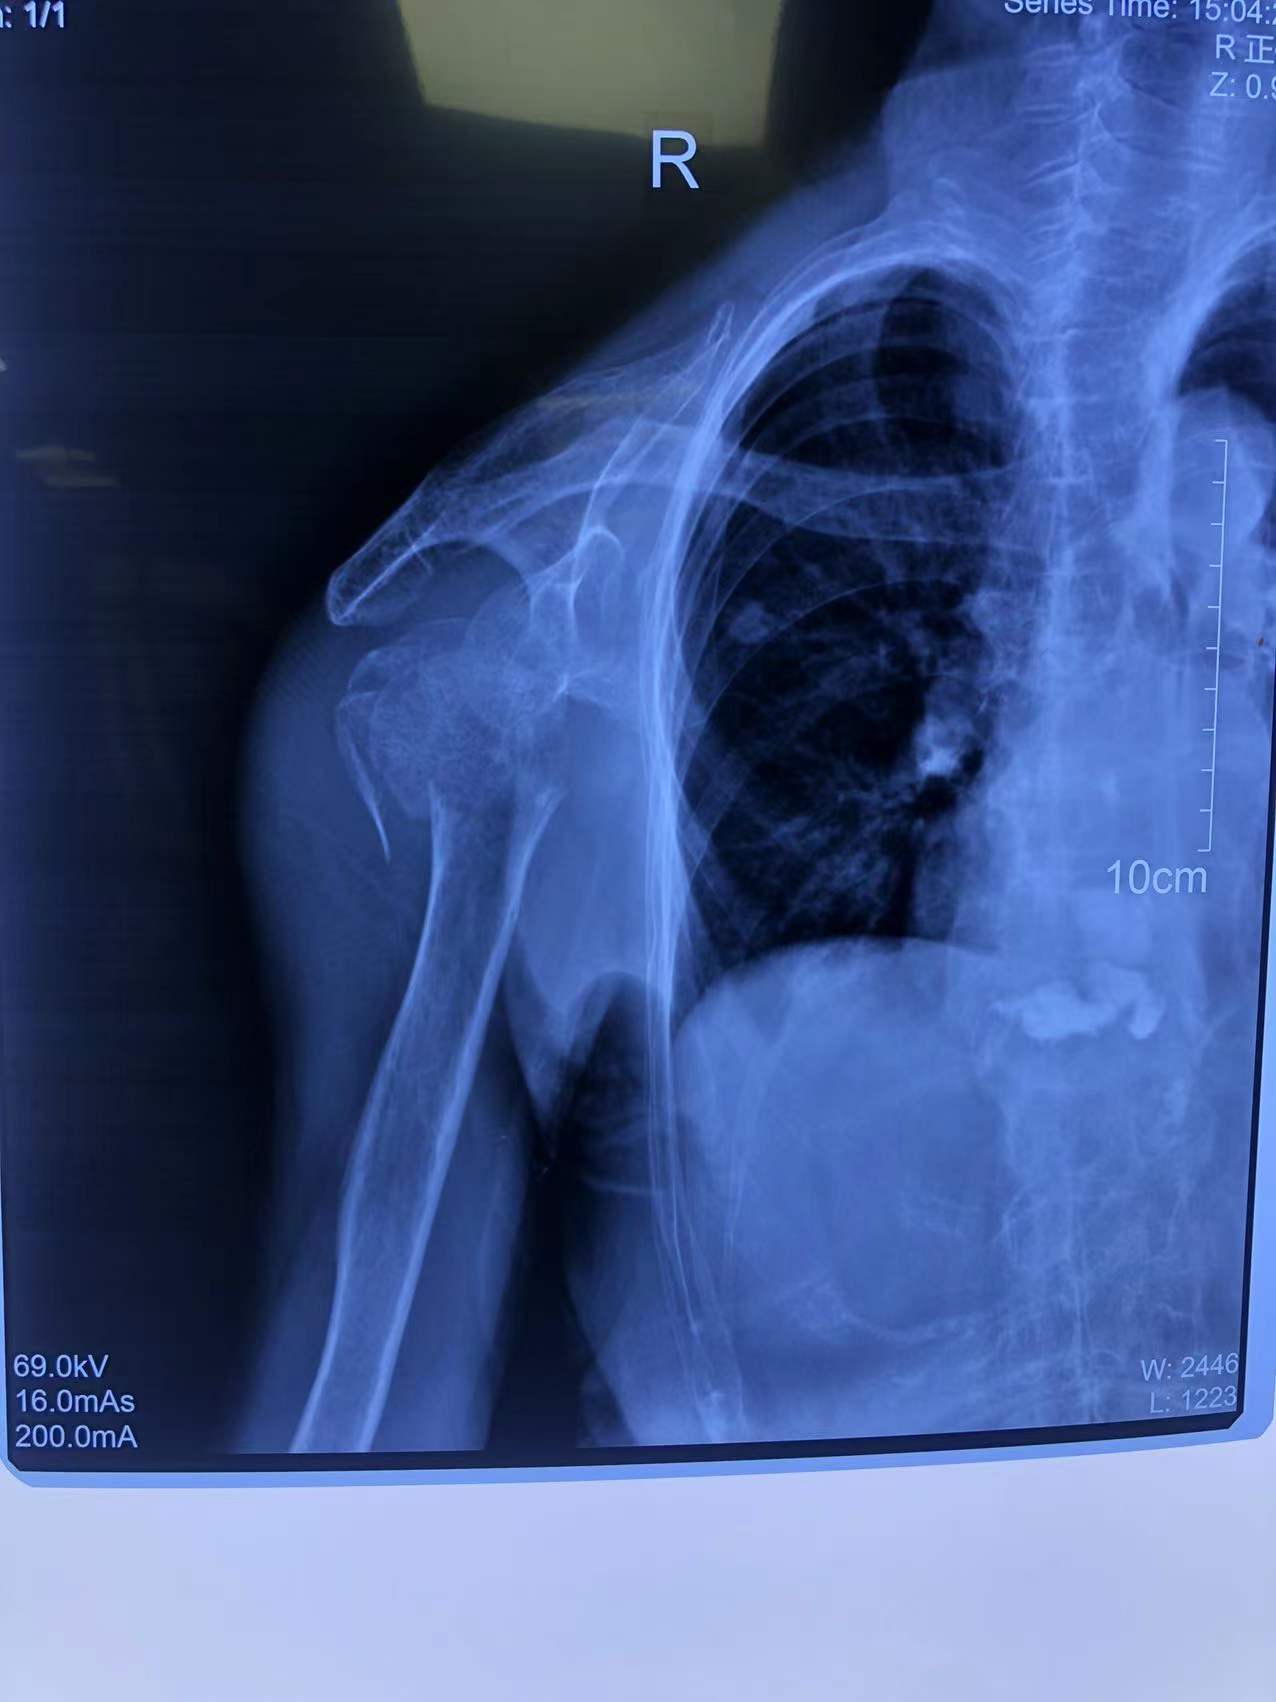

80歲的李老太(化名)走路時不慎摔了一跤,雖然感覺右肩膀和上臂疼痛劇烈,但她想著休息休息就沒事兒了,便沒有第一時間前往醫(yī)院看診。然而,接下來的幾天,疼痛不但沒有好轉(zhuǎn),反而愈演愈烈,這才被家人著急忙慌送到了石化醫(yī)院。行右肩X線檢查,原來,李老太右肱骨近端粉碎性骨折,隨后收住骨科。

李老太是粉碎性骨折,情況較為嚴重,為恢復(fù)肩關(guān)節(jié)功能,石化醫(yī)院骨科副主任張明龍帶領(lǐng)團隊充分評估病情,與病人和家屬協(xié)商后,決定實施人工肱骨頭置換術(shù),在右肩安裝一個“人工肩關(guān)節(jié)”。